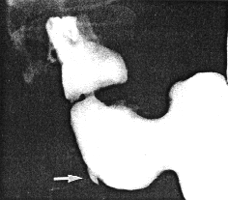

Case 22.1. M.W., 55 year old female, complained of cramp-like epigastric pains diurnally and occasionally nocturnally after a late evening meal. At times she felt nauseous. Physical examination revealed signs of chronic bronchitis and iron deficiency anaemia. Gastroscopy showed a sliding hiatus hernia without oesophagitis. No evidence of ulceration or other lesion was seen in the stomach and duodenum. A second gastroscopy six years later showed no abnormality in the oesophagus, stomach and duodenum. Repeat gastroscopy the following month was difficult due to lack of patient co-operation. The oesophagus was normal. The pyloric region appeared somewhat hyperaemic and oedematous, the remainder of the stomach being normal. The duodenum could not be visualized. Barium radiographic examination at that time showed a small diverticulum on the greater curvature of the pyloric sphincteric cylinder approximately 2.5 cm proximal to the pyloric ring (Fig. 22.1A). Its neck, which was surrounded by a shallow, smooth-walled indentation of the barium in the lumen, was 0.7 mm in diameter. During contraction of the cylinder it was seen to be situated midway between the right and left pyloric loops (Fig. 22.1B) in the situation where the pyloric pseudo-diverticulum occurs normally (Chap. 13). At times, during near maximal contraction of the cylinder, it disappeared, only to reappear during the next cycle of filling.

| Fig. 22.1. A Case M.W. Small intramural diverticulum (arrow) on greater curvature of pyloric sphincteric cylinder 2.5 cm proximal to pyloric ring. B Case M.W. Partial contraction of sphincteric cylinder. Intramural diverticulum (arrow) situated on rim of physiological pseudodiverticulum (PD), midway between right and left pyloric loops | |

Because of the features enumerated in the discussion it was diagnosed as an intramural or partial gastric diverticulum. It was certainly not an ulcer as witnessed by repeated gastroscopies. The fact that it was not seen at gastroscopy does not come as a surprise as Treichel et al. (l976) had found that the lesion was easier to detect by radiography than by endoscopy. Cockrell et al. (l984) stated that an intramural diverticulum may be difficult to detect endoscopically if its ostium is hidden by a fold or if it occurs in an area which is contracting.